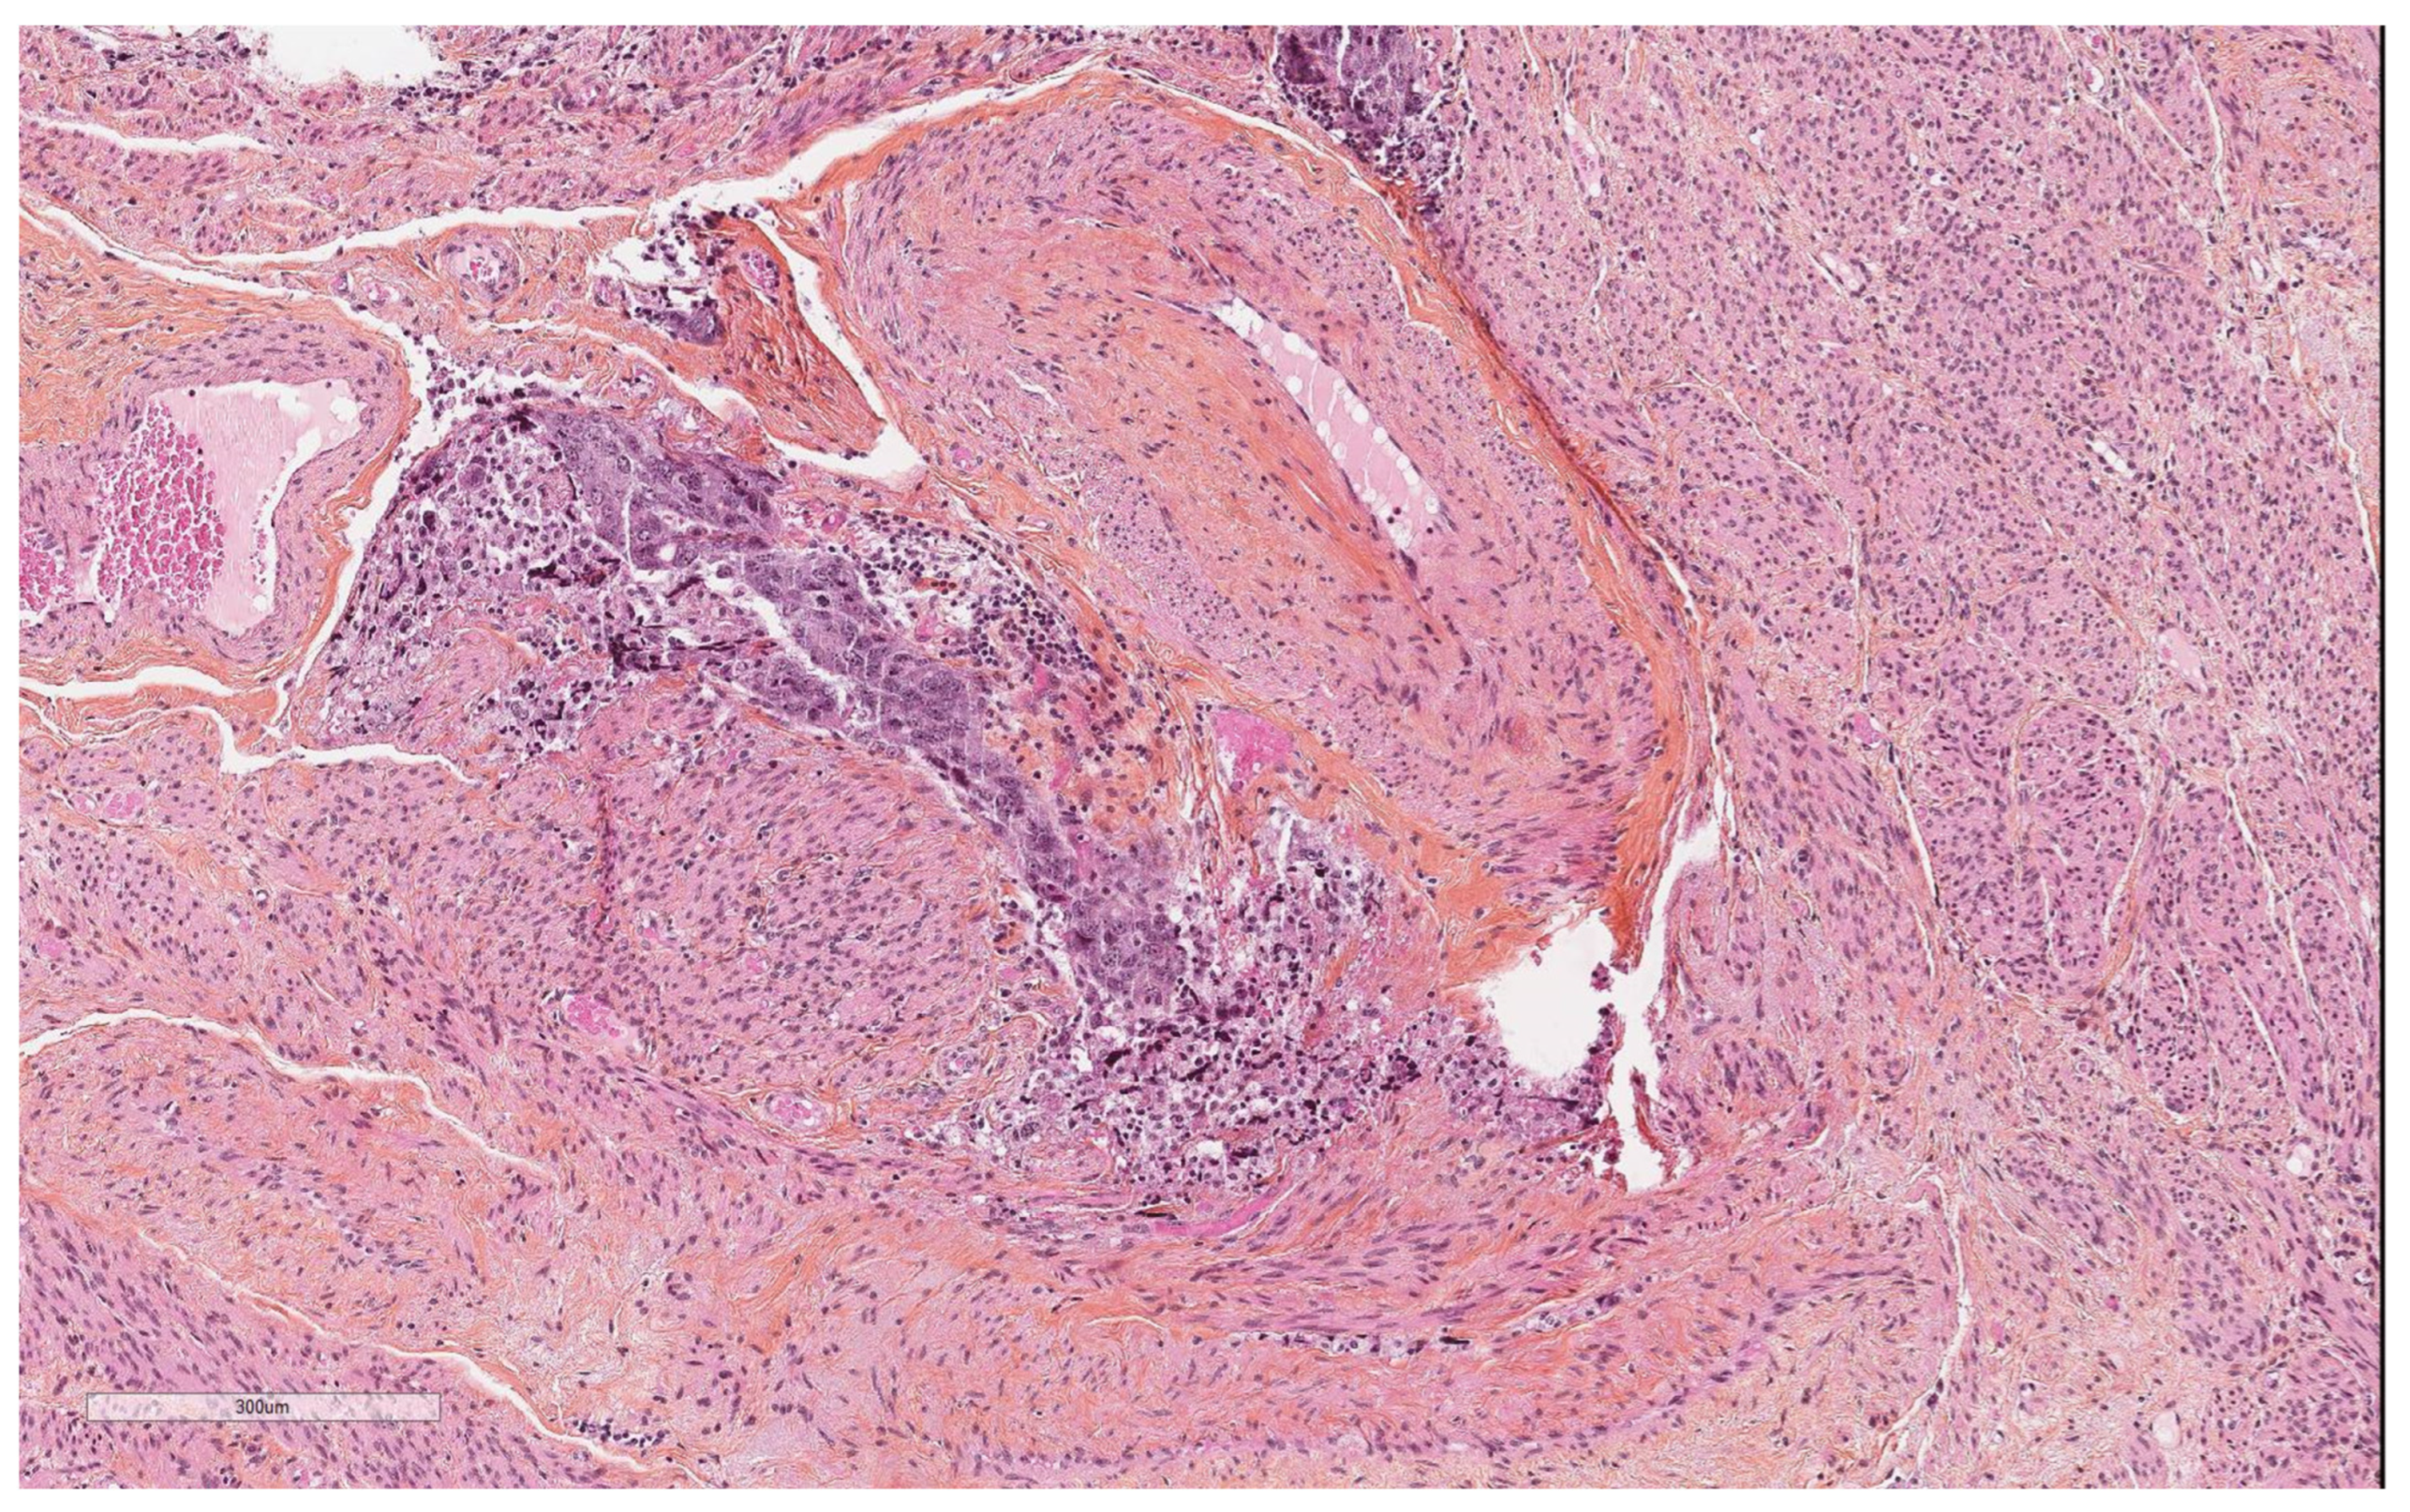

Artefacts in Hysterectomies with a Special Focus on Vascular Pseudoinvasion

| True vascular emboli | |

| Present | 11 (18.3) |

| Absent | 49 (81.7) |

| Tumor necrosis | |

| Present | 17 (28.3) |

| Absent | 43 (71.7) |